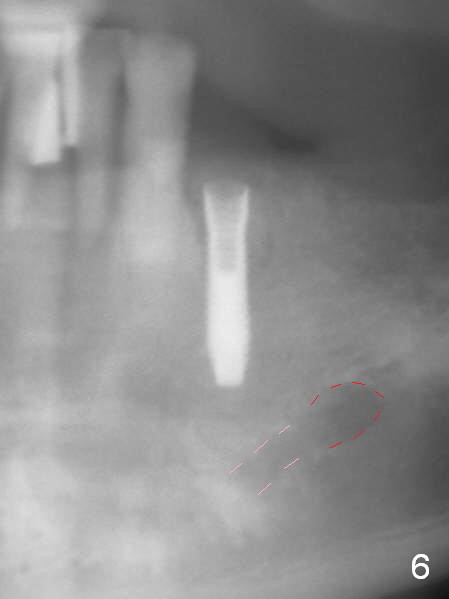

A 72-year-old man presents to clinic for implants because of pain associated with wearing the lower partial. The teeth #21, 24, 25 and 31 seem to be non-salvageable and are going to be replaced by implants so that the lower RPD can be reused (Fig.1). The edentulous ridge is atrophic (Fig.9 *). The upper complete denture appears to be functional. Since the tooth #21 is symptomatic (Fig.2) and the patient has chronic TMJ dislocation, the affected tooth is extracted first (Without antibiotic socket treatment) for immediate implant (Fig.3 (1.5 mm drill (placed more lingually)). The lower RPD is used as a surgical guide (Fig.4 (3 mm drill in place)). When a 3.8x16 mm implant is placed with bone graft (Fig.5 *), the underlying neurovascular bundle is undetected. A small field of panoramic X-ray is retaken; it seems that there is enough clearance from the Mental Foramen (Fig.2,6,7 (red dashed line)) and the Incisive Canal (pink dashed line). The implant is then placed 2 mm more apically (Fig.7) to reduce the chance of periimplantitis since the buccal plate is lost. A 5.5x5(5) mm abutment is placed (Fig.5) with more graft. The access of the abutment is left open so that a part of periodontal dressing is inserted for additional retention (Fig.8,9). The RPD is placed back for adaptation of the dressing. The patient is advised not to wear the RPD postop to reduce micromovement.